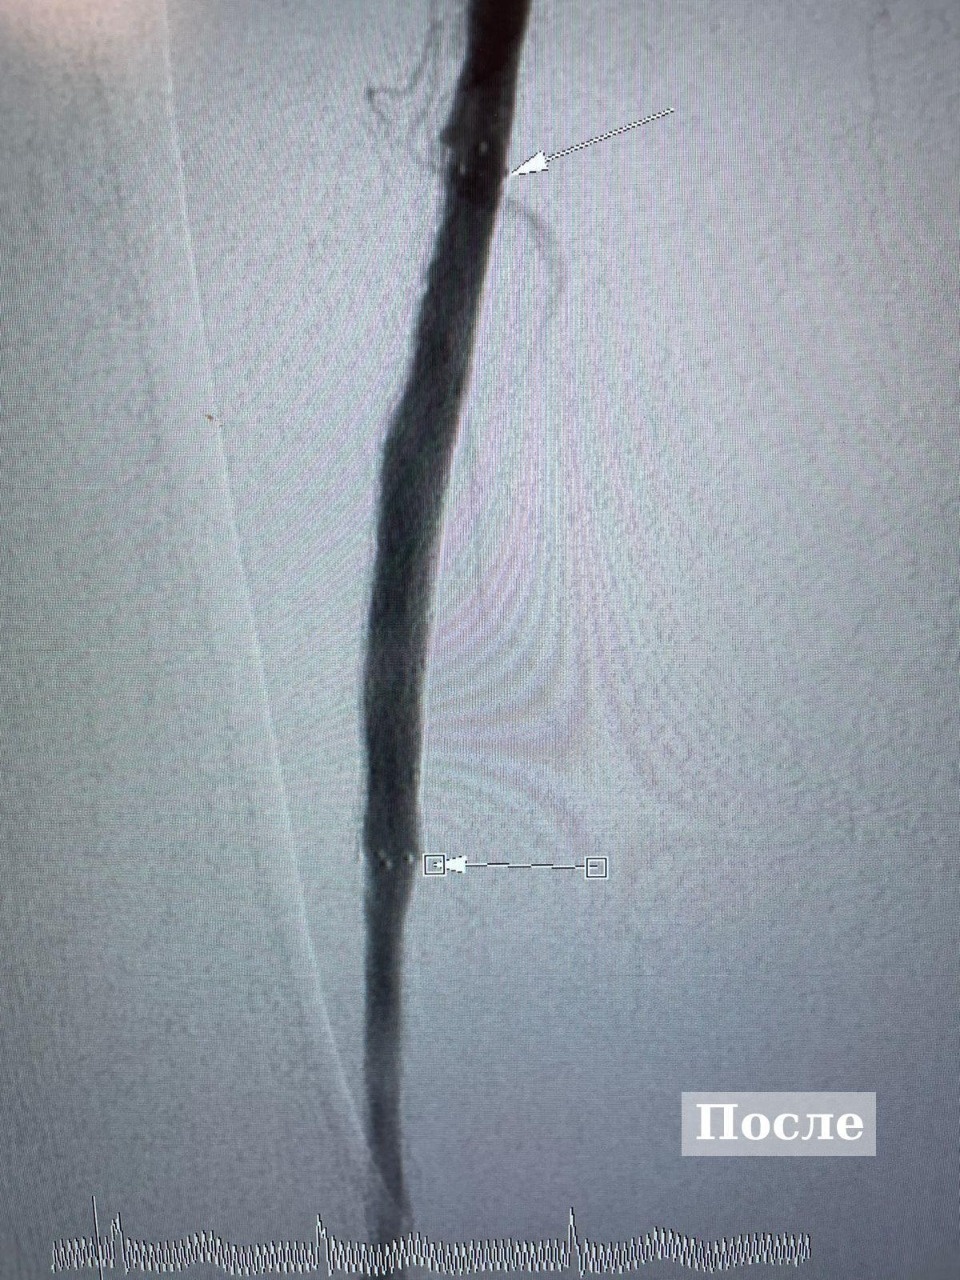

90-летней пациентке провели высокотехнологичную операцию на артериях в Великих Луках

Фото: комитет по здравоохранению Псковской области

Операцию сделали в отделении рентгено-хирургических методов диагностики и лечения Великолукской межрайонной больницы. У пожилой пациентки развивалась гангрена на правой ноге.

Заведующий РХМДиЛ Алексей Горин поделился, что для сохранения конечности специалисты решили провести пенсионерке малоинвазивную операцию с имплантацией стента, в результате у пациентки восстановилась проходимость артерии.